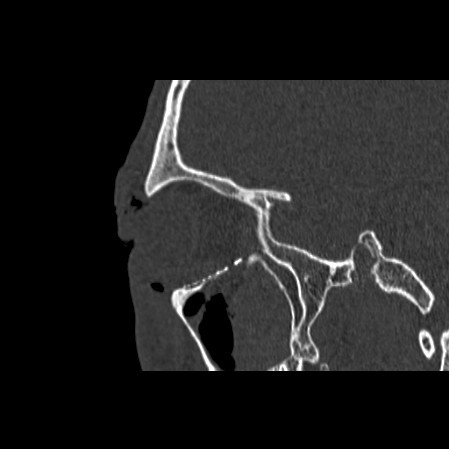

Facial Fracture X-Rays